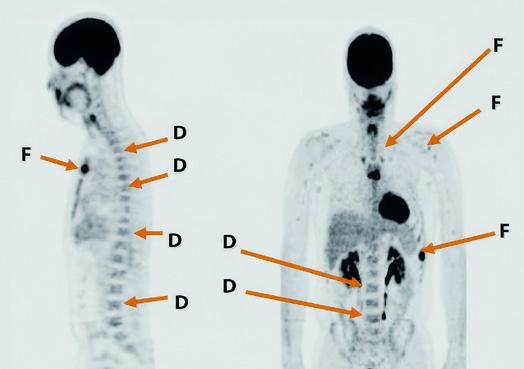

Positron emission tomography (PET) scanning is a “real-time” study that shows where, and to what extent, cancer cells are actively dividing in the body.

Before a PET scan, a patient is injected with a sugar-fluorine compound (FDG, or fluorodeoxyglucose) that is taken up by the body’s actively multiplying cells as fuel for cell division. When the body is scanned, the areas with the highest concentration of sugar-fluorine uptake glow from positrons emitted by the fluorine, revealing “hot spots” where rapid metabolism can indicate areas of active cancer cell division. This scan covers the whole body and is very sensitive in detecting potential tumor activity. It is measured in units of Standardized Uptake Value (SUV).

Figure

PET-CT is a highly accurate and valuable imaging technique used in diagnosis, therapy assessment, and prognosis of myeloma. It combines PET scan with CT in areas where there is high uptake of FDG. It provides information both about past damage and current myeloma activity, thus enabling the doctor to study changes over time. Because of its sensitivity and its ability to detect disease in areas outside the bone marrow, PET-CT has been included along with specialized testing of the bone marrow biopsy specimen to establish MRD-negative status following treatment.

The advantages of PET imaging include its ability to:

¡ Assess metabolic response to therapy. PET-CT is the preferred imaging study in this setting.

¡ Assess the status of patients with non-secretory myeloma, whose disease cannot be monitored with standard blood and urine tests.

¡ Detect lytic bone lesions at diagnosis as a baseline test before therapy.

¡ Predict progression-free survival (PFS) and overall survival (OS). Three or more PET-positive lesions are an independent predictor of poorer PFS and OS.

Disadvantages of PET include the following:

¡ It is time-consuming and expensive.

¡ Because areas of infection and inflammation can also take up FDG, PET scans can produce false-positive readings for cancer.

¡ There is some concern that skull lesions could be missed because of the normally high FDG uptake in the brain.

¡ As with MRI, therapy can interfere with PET results. Patients should not start therapy before a scheduled PET scan. Dexamethasone in particular is problematic.

Dexamethasone interferes with PET results by slowing down the entry of glucose into tumor cells. PET studies used to determine the effect of treatment should not be performed until after the patient has been off dexamethasone for 2–3 weeks, and before the patient starts the next cycle of dexamethasone.

Figure 14. F-fluorodeoxyglucose (FDG) PET-CT showing diffuse (D) and focal (F) myeloma lesions